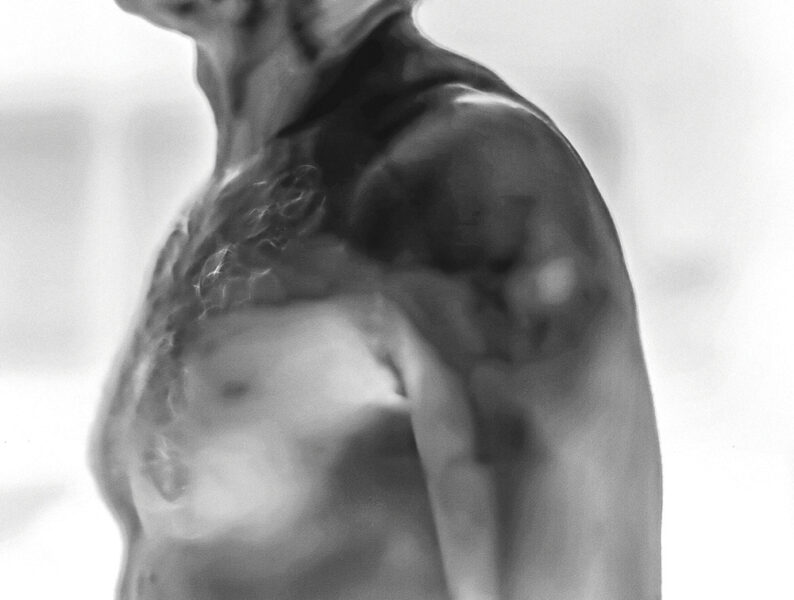

Injection Site addresses the politically charged global medical crisis of COVID-19. The project involved the use of a high-resolution thermal camera to photograph the arms of participants after vaccination. This has resulted in images over 130 participants, each image documenting and creating a visual trace of each person’s reaction to the vaccine. Rather than providing a simple scientific record, the ethereal images serve as evocative statements about individuality and our collective humanity. This project was intended to avoid being a polemic statement, but rather to cause pause for thought, to ignite conversation, and promote a mutual consideration for the actions and feeling of others, during a period when the health and wellbeing for all of us was such a contentious and divisive issue.